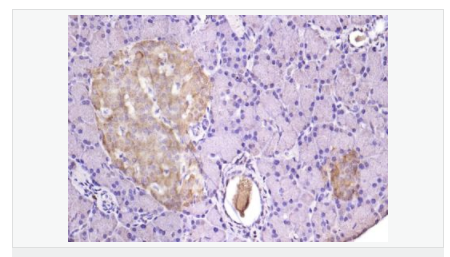

image.png

產(chǎn)品介紹TMED4 is a putative NF-kB activating protein belonging to the EMP24/GP25L family, and contains 1 GOLD domain. It is also known as Transmembrane emp24 protein transport domain containing 4.

Involved in vesicular protein trafficking, mainly in the early secretory pathway. targeting. Involved in the maintenance of the Golgi apparatus. Appears to play a role in the biosynthesis of secreted cargo including processing. Involved in endoplasmic reticulum stress response. May play a role in the regulation of heat-shock response and apoptosis

Subcellular Location: